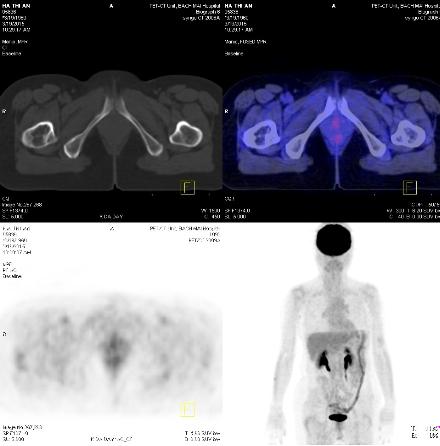

Chụp PET/CT đánh giá lại: Thành dạ dày tăng hấp thu 18F-FDG nhẹ, sỏi đường mật ngoài gan, tổn thương vùng cổ xương đùi phải không tăng hấp thu 18F-FDG. Không thấy hình ảnh tăng hấp thu và chuyển hóa 18F-FDG bất thường tại các vị trí khác trong cơ thể.

Chụp PET/CT: Không thấy hình ảnh tăng hấp thu và chuyển hóa bất thường 18F-FDG trong cơ thể.

Hình 12: Không thấy hình ảnh tăng hấp thu 18F-FDG tại vùng hạch thượng đòn 2 bên.

Hình 13: Không thấy hình ảnh tăng hấp thu 18F-FDG tại hạch ổ bụng.

Hình 14: Không thấy hình ảnh tăng hấp thu 18F-FDG tại vùng cổ xương đùi phải.